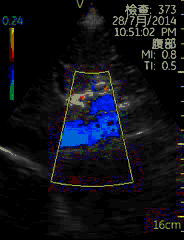

Vscan临床图片 腹部